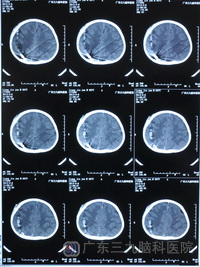

完善相关检查后,2月7日下午,广东三九脑科医院神经外五科主任鲁明利用先进的影像导航设备在全麻下为小虎行“右侧枕叶金属异物取出术”,几经努力,终于探查见一直径约1厘米的有锈迹的圆形钢珠,并成功将钢珠取出。术后小虎康复良好,并将于近日出院。

术前CT 术后CT